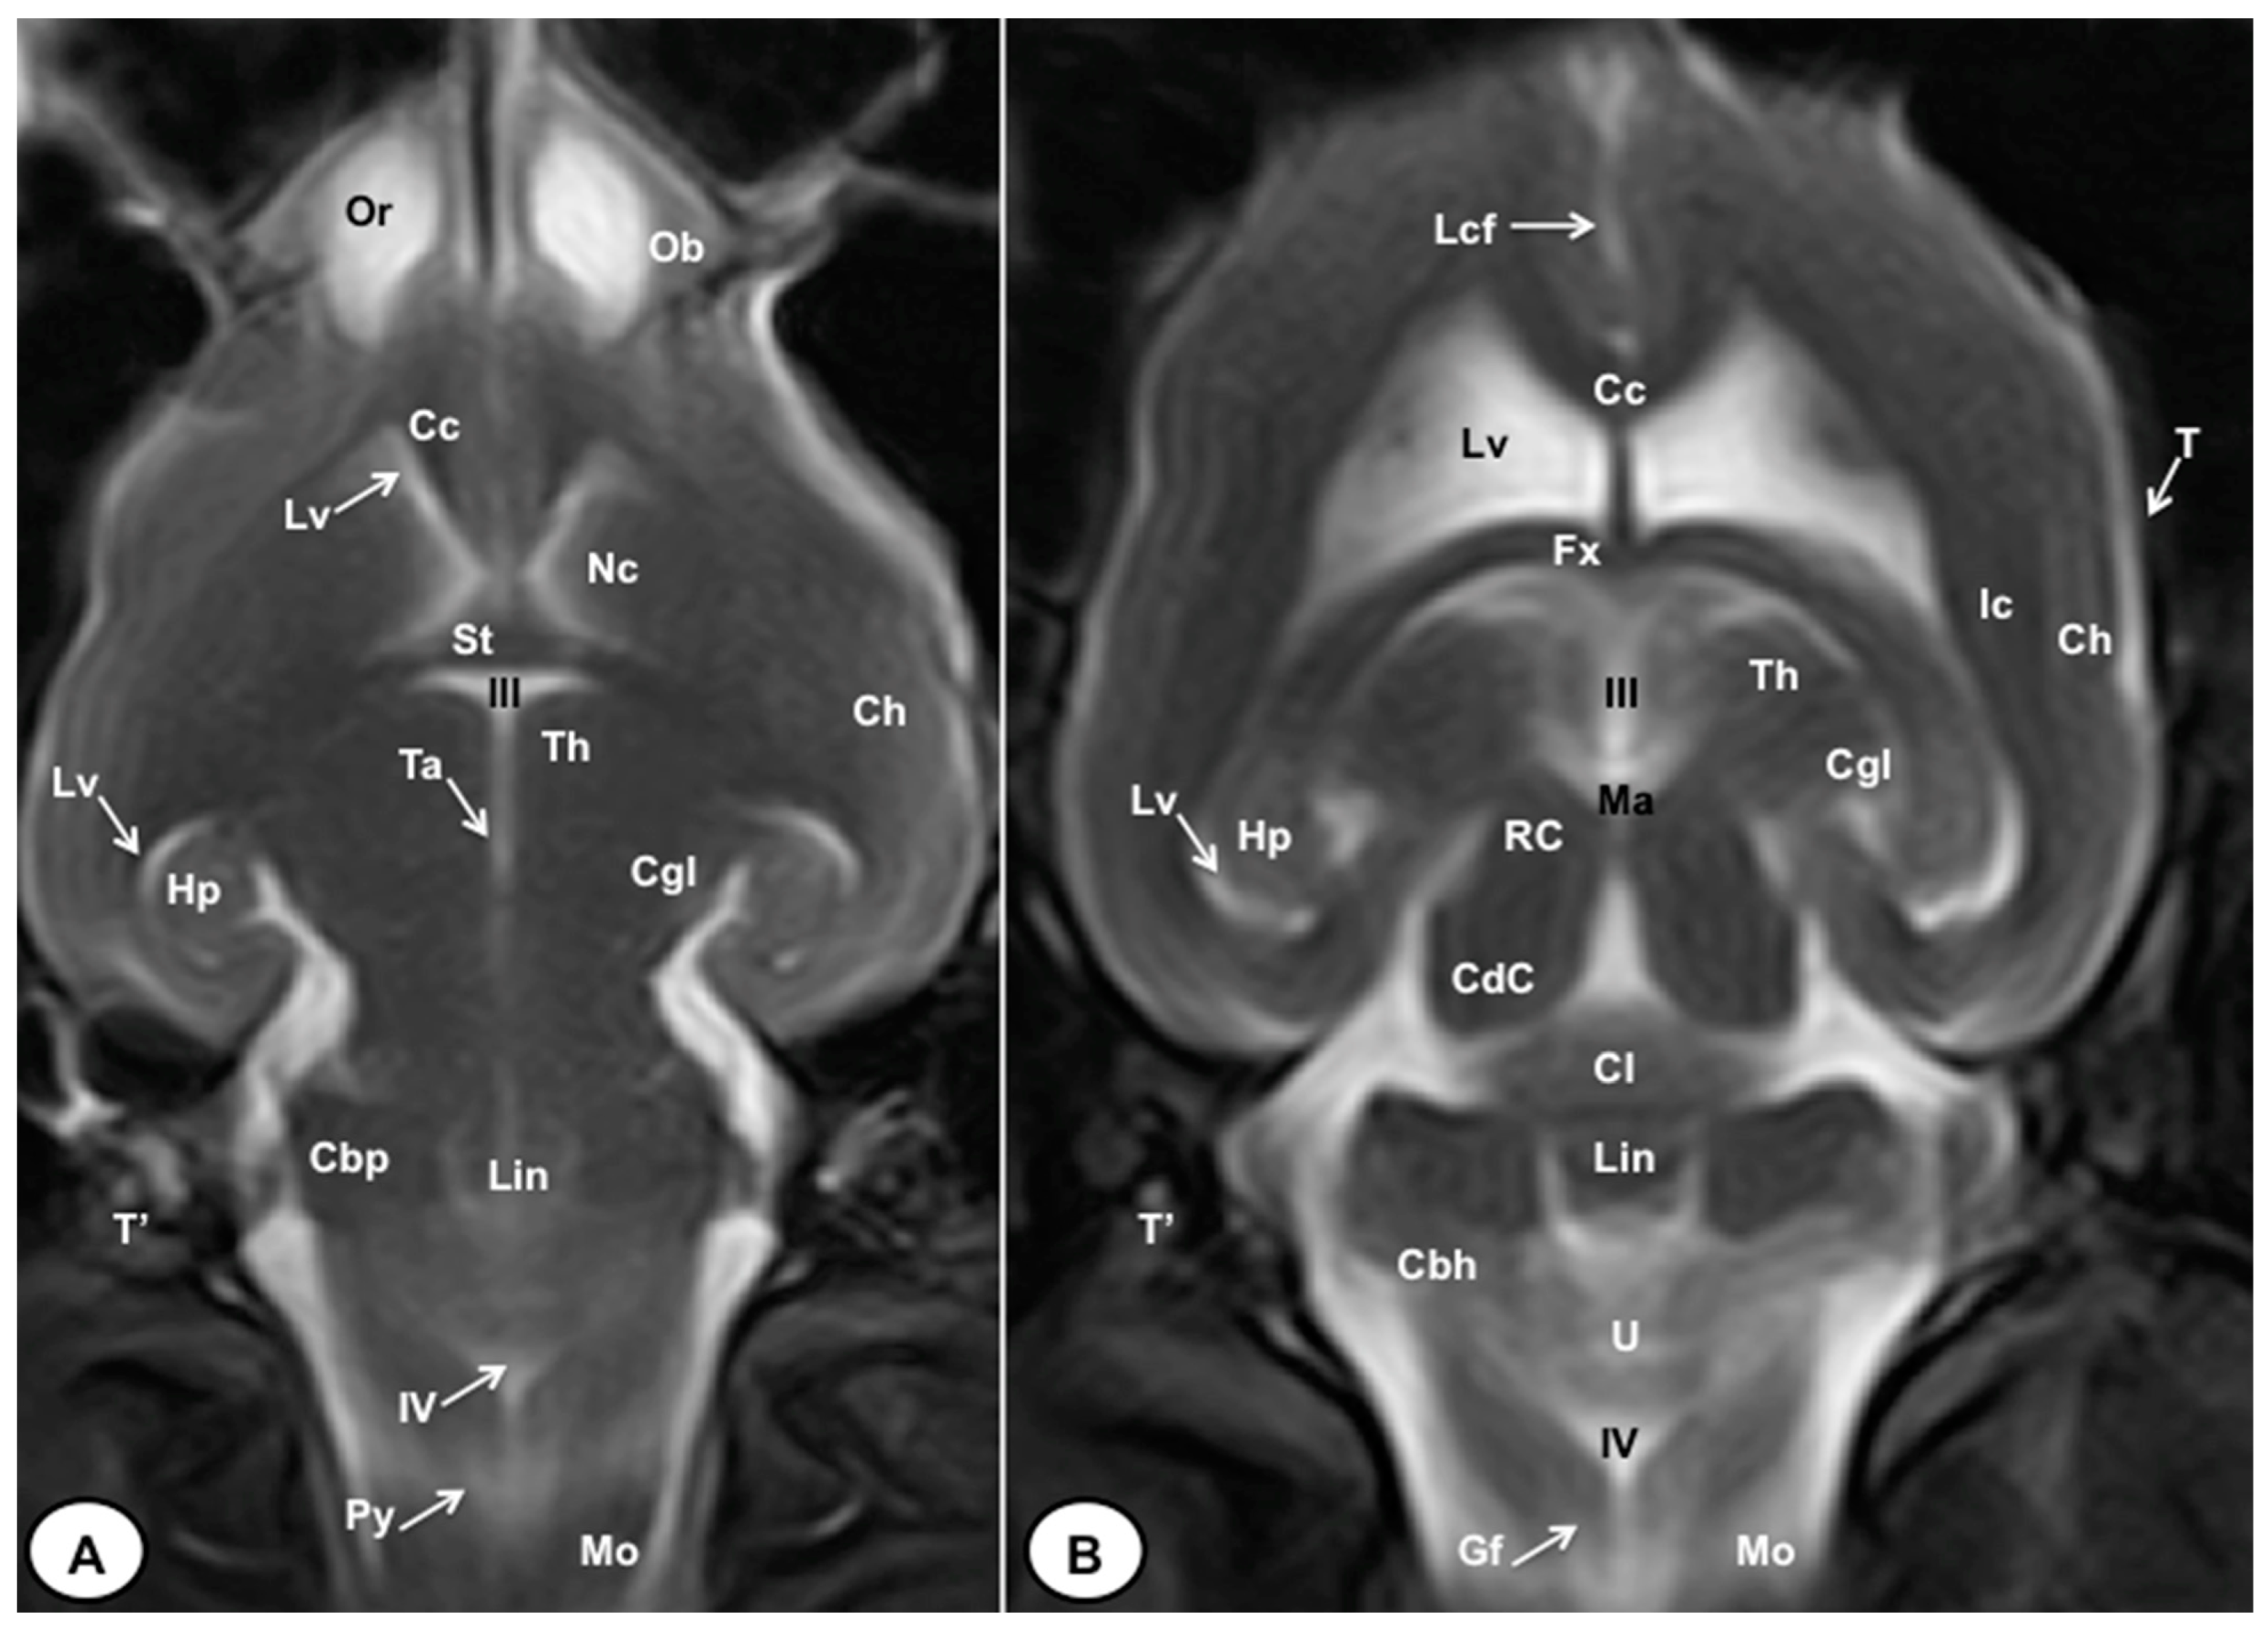

3.2. Magnetic Resonance Imaging (MRI)